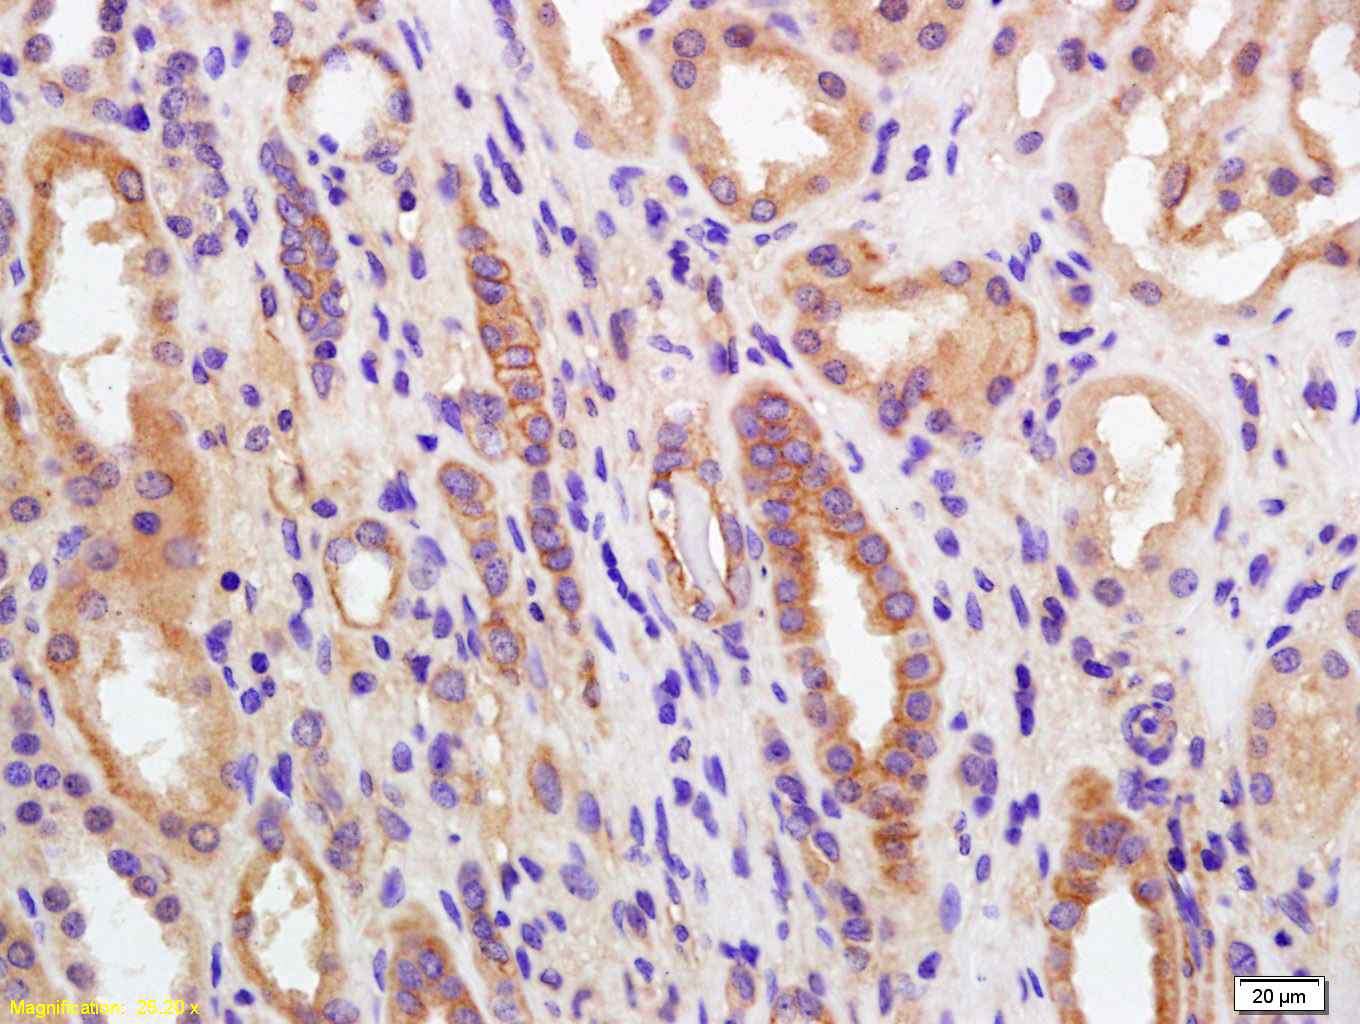

Tissue/cell: human kidney tissue; 4% Paraformaldehyde-fixed and paraffin-embedded; Antigen retrieval: citrate buffer ( 0.01M, pH 6.0 ), Boiling bathing for 15min; Block endogenous peroxidase by 3% Hydrogen peroxide for 30min; Blocking buffer (normal goat serum,C-0005) at 37℃ for 20 min; Incubation: Anti-PGRMC Polyclonal Antibody, Unconjugated(bs-5922R) 1:200, overnight at 4°C, followed by conjugation to the secondary antibody(SP-0023) and DAB(C-0010) staining